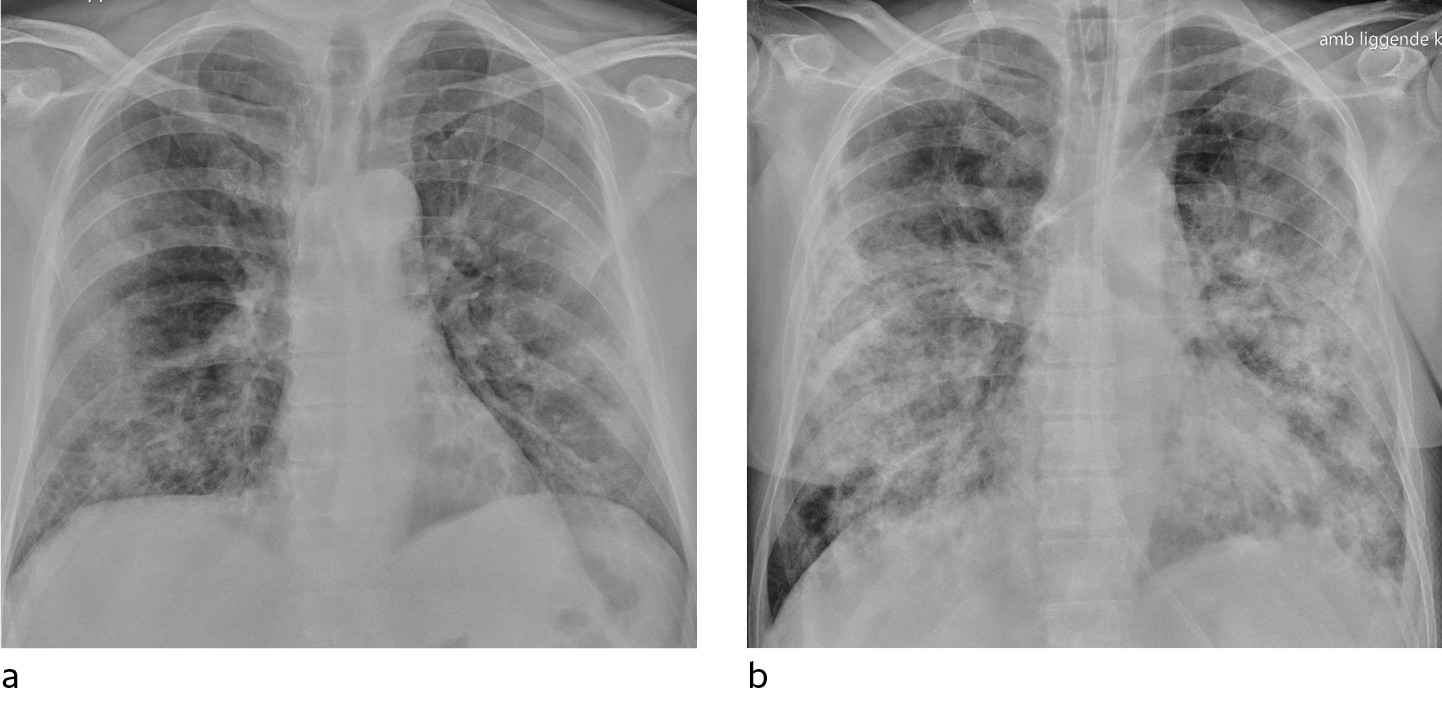

I et materiale fra Hongkong hadde 69 % funn på røntgen thorax før behandling (baseline), men 9 % hadde funn på røntgen thorax før positiv PCR (14). Sensitiviteten for røntgen thorax var 69 % og for PCR 91 %. Vanligste røntgenfunn var bilateral konsolidering og mattglassfortetninger med perifer og kaudal distribusjon. Forandringene var mest uttalt 10–12 dager etter symptomdebut. Figur 1 og figur 2 viser typiske funn på røntgen thorax ved covid-19.

Hos inneliggende pasienter kan et sengebilde i tidlig stadium være nyttig som sammenligningsgrunnlag for tolking av bilder tatt senere. Hos pasienter med alvorlig sykdom vil det være indisert med sengebilder for kontroll av medisinskteknisk utstyr (figur 3), men det er ikke indisert med daglig, rutinemessig røntgen thorax hos stabile pasienter. I forløpet av sykdommen vil det være indisert med sengebilde ved mistanke om komplikasjoner og ved oppfølging og monitorering av sykdomsprogresjon.